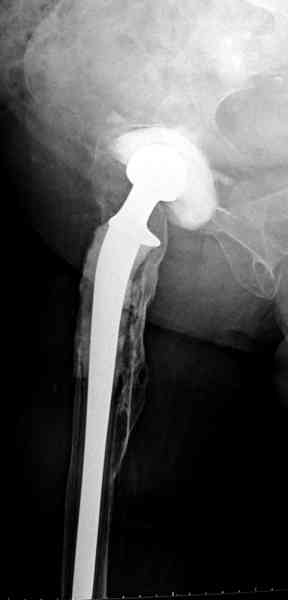

Приглашенный хирург установил ревизионный вариант бедренного компонента без замены ацетабулярного компонента, что осложнилось нагноением и свищами на уровне сустава и средней трети бедра. После двухгодичного безуспешного лечения перевязками и антибиотиками больная обратилась к нам на консультацию.

Повторная операция по удалению тотального протеза с irrigation&debridment, канал после очистки цемента обильно промыт и рассверлен римером.

Приготовлен цемент из расчета: Tobramycin 2.4 g (2 флакона), Vancomycin 2 млн (4 флакона) и 2 упаковки цемента с добавлением дополнительного флакона цементной жидкости.

После обработки ацетабулярного компонента, ещё в мягком цементе в полости вертлужной впадины головкой бедренного компонента сделана выемка для головки, чтобы свежий цемент не прилипал к головке. Головку бедренного компонента завернул обычной стерильной фольгой, которую после образования выемки отлепил от головки.

Для спейсера в бедро использовал старый длинный бедренний компонент меньшего диаметра, облепленный со всех сторон цементом с антибиотиком.

№3-6 снимки с осложнением

и последние снимки.